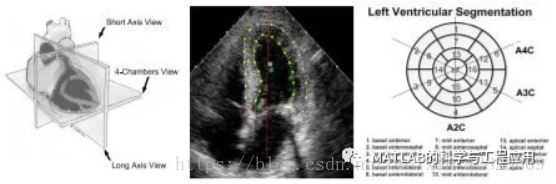

冠心病可以通过评估左心室超声图像中心壁的区域运动来诊断。

Coronary Heart Disease can be diagnosed byassessing the regional motion of the heart walls in ultrasound images of theleft ventricle.

以前的研究工作表明,为了解决这个问题,需要考虑不同心脏区域之间的相互作用及其对心脏临床状况的总体影响。

Previous work indicates that in order toapproach this problem, the interactions between the different heart regions andtheir overall influence on the clinical condition of the heart need to beconsidered.